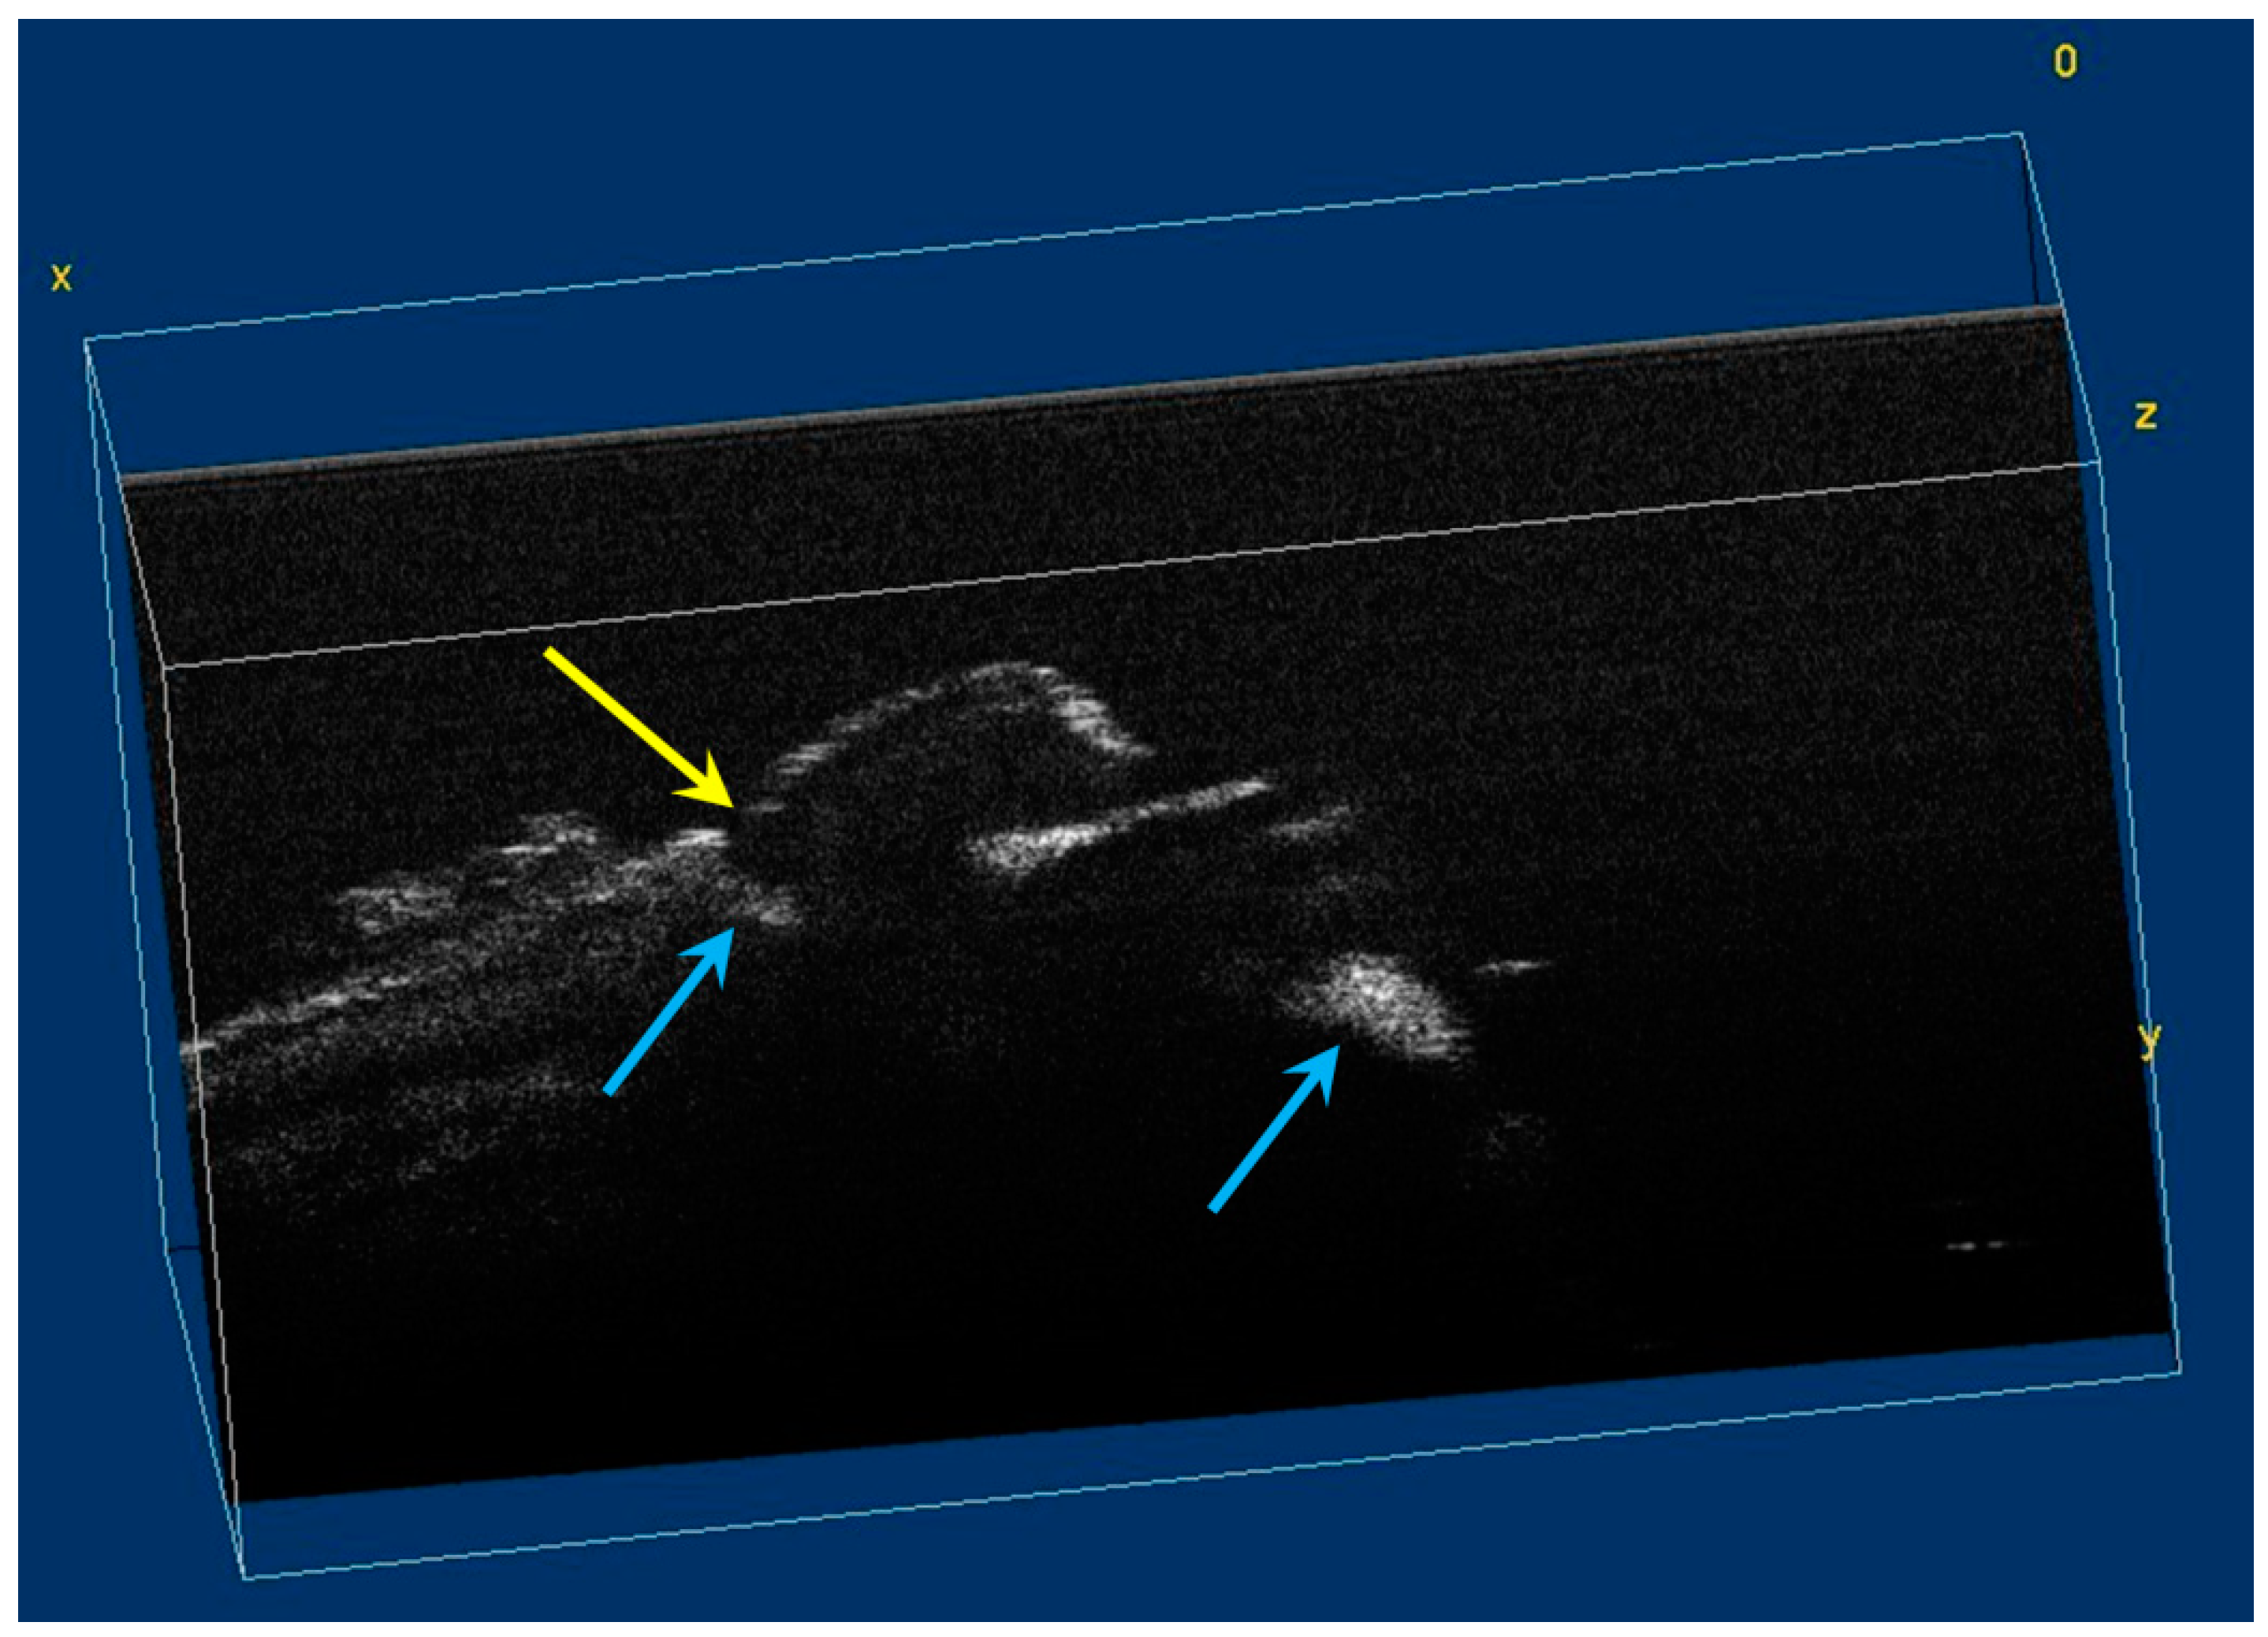

The image processing using ImageJ software showed the spatial disposition and extent of the hypomineralization lesions and hypoplasia (Figure 6, Figure 7, Figure 8 and Figure 9).

Figure 7.

Volumetric reconstruction (in ImageJ) of hypomineralization areas marked by blue arrows. The yellow arrow indicates a small hypoplasia lesion, which was not initially identified in 2D OCT images analysis.